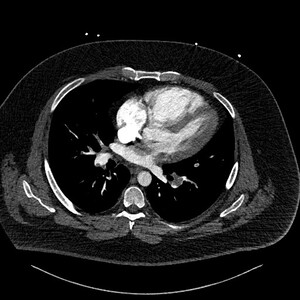

Figure 3 is the axial slice below and shows an elongated low attenuation and homogenous structure extending across a defect in the IAS into the left atrium (short arrow) and when viewed in contiguous slices was inseparable from the RA filling defect. This represented intracardiac thrombus in transit (ICTIT). There were further low attenuation, homogenous and well defined filling defects (medium white arrow) in the left atrium (LA). The radiologist also noted that the right heart chambers were enlarged compared to the left, and that both the IAS and interventricular septum (IVS) were inversely bowed toward the left – these are CTPA features that can indicate elevated right heart pressures and therefore right heart strain in the clinical context of PE.